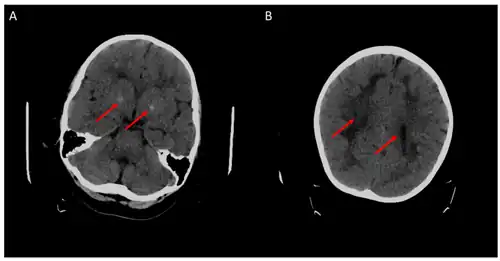

Children with the FOLR1 mutation are born healthy. Symptoms typically appear at about 5 to 24 months of age. The symptoms get worse with time. Without treatment there may be poor muscle tone, trouble with coordination, trouble talking, and seizures.[2][3] In addition, signs of psychomotor retardation, sleep disturbances, cerebellar ataxia, and delayed development of head growth can occur. At around age three, visual disturbances can develop, and sensorineural hearing loss can occur at around age six.[11] In children with cerebral folate deficiency, the cerebrospinal fluid shows low levels of 5MTHF, and a loss of white matter in the brain (leukodystrophy) may occur. As a result of the decreased levels of 5MTHF, the child experiences low levels of Vitamin B folate.[12] There is inability for the 5MTHF to be transported across the blood-brain barrier, resulting in symptoms of seizures, delayed cognitive and motor processing, and autistic features.[13]

- ^ a b Mafi S, Laroche-Raynaud C, Chazelas P, Lia AS, Derouault P, Sturtz F, Baaj Y, Froget R, Rio M, Benoist JF, Poumeaud F, Favreau F, Faye PA (October 2020). "Pharmacoresistant Epilepsy in Childhood: Think of the Cerebral Folate Deficiency, a Treatable Disease". Brain Sciences. 10 (11): 762. doi:10.3390/brainsci10110762. PMC 7690394. PMID 33105619.